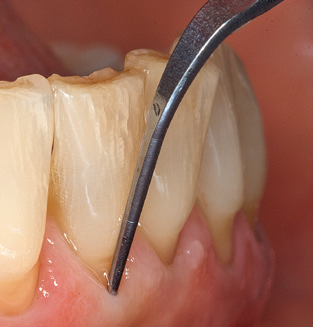

L'attuale piano di lavoro per SPT

Naturalmente, l'uso di strumenti per la rimozione meccanica del biofilm è una componente centrale di SPT e quindi di importanza primaria. Di conseguenza, il flusso di lavoro SPT comprende sia la pulizia sopra-gengivale che sub-gengivale. Nel nostro piano di lavoro, una combinazione di strumenti manuali e

di dispositivi per la pulizia meccanica si è dimostrata vantaggiosa. Sono disponibili diverse opzioni per le procedure meccaniche: dispositivi sonici, dispositivi ad ultrasuoni e dispositivi di air-polishing.

Una buona illuminazione del campo di lavoro facilita notevolmente il processo. Il sistema utilizzato dagli autori ottiene questo risultato grazie a un anello LED 5x integrato nel manipolo. Naturalmente, viene offerta anche una serie di consigli di lavoro per diverse indicazioni. Un inserto diritto, utilizzabile universalmente, è lo strumento di base necessario per la pulizia meccanica dei denti naturali (Fig. 5a e b). Sono disponibili anche inserti curvi, che consentono l'accesso alle forcazioni esposte, per le aree difficili da raggiungere nella regione posteriore (Fig. 6).

Naturalmente, anche i consigli di lavoro per la pulizia delle superfici degli impianti sono indispensabili per SPT nei pazienti dotati di impianti. L'inserto per la pulizia dell'impianto in questo casoi è caratterizzato dal suo design affusolato ed esagonale. Questo design consente una penetrazione leggera e atraumatica nella tasca perimplantare e mostra buone prestazioni di pulizia (Fig. 7).